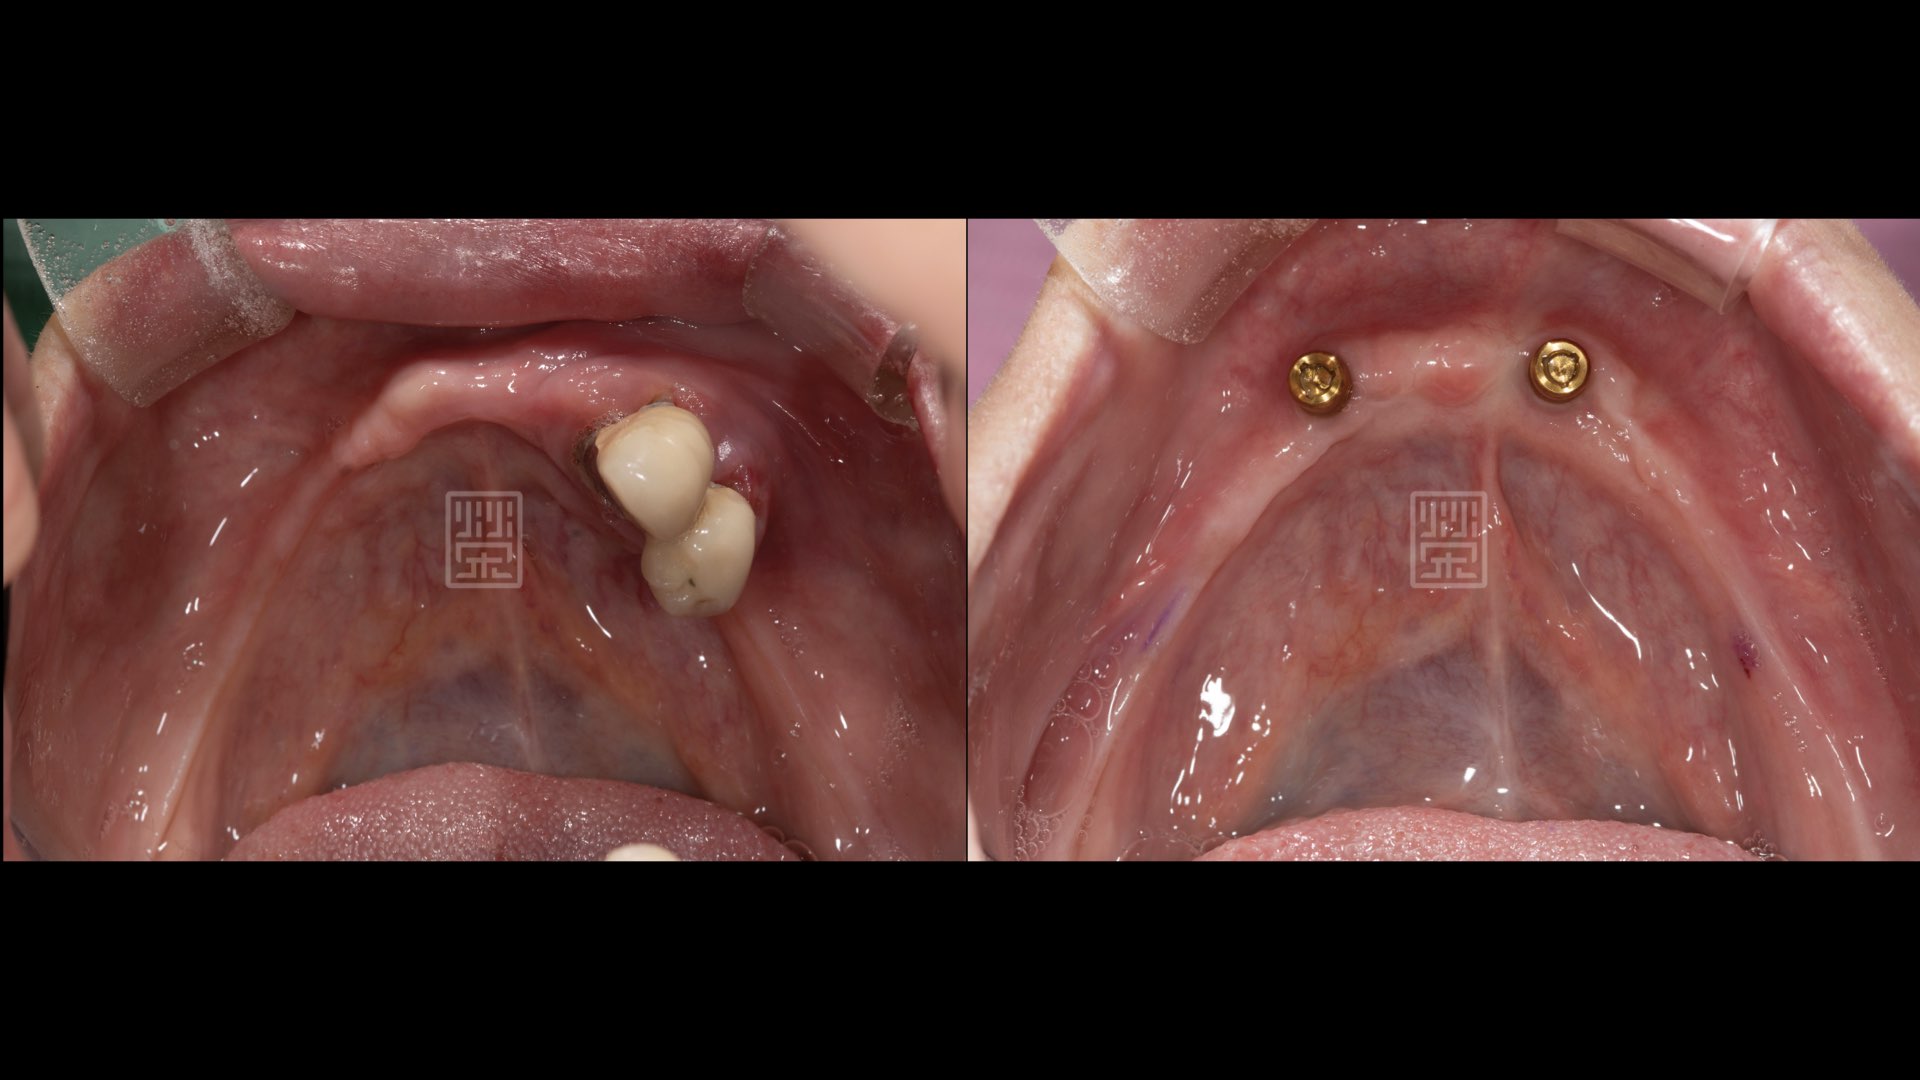

榮醫師檢查後發現舊義齒下方的牙根很不好,加上下顎因為長期缺牙,所以牙齦齒槽骨萎縮很嚴重,榮醫師建議上顎移除所有不良牙根,下顎移除不良牙根後,再放兩個植牙,利用覆蓋式植牙活動義齒,恢復功能與美觀。

利用兩顆植牙穩定全口義齒